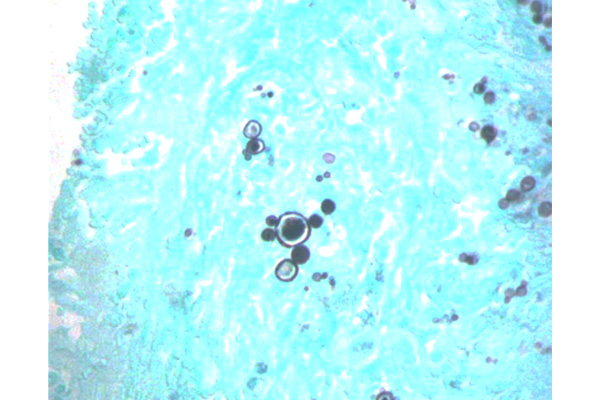

Con impregnación argéntica de Grocott (GMS) se ponen en evidencia las características de este hongo: son levaduras grandes, esféricas u ovoides, con pared gruesa y birrefringente, cuyo tamaño oscila entre 10 – 30µm, pudiendo alcanzar hasta 60µm.

El patrón distintivo es la gemación múltiple, con brotes adheridos a la célula madre. Esto crea una imagen clásica de «rueda de timón» (timón de barco o rueda dentada), aunque también pueden verse brotes simples.